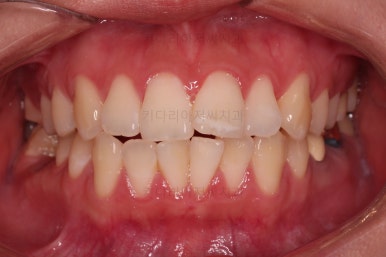

마찬가지로 초진 시 입안의 모습입니다.

입안 사진을 보니 문제점이 보이죠.

바로 어금니가 없는 상태였습니다.

물론 치열도 그리 많이 삐뚠 편은 아니고, 치아가 없으니 심플하게 임플란트를 해 넣으면 되지 않겠나 라고 생각할 수 있지만요.